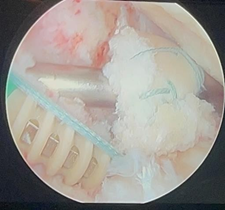

Peripheral fixation of the meniscus

Subsequently, the All-inside sutures begin to be placed. We prefer to use the Smith & Nephew Fast- Fix system. We start at the posterior horn and the middle part of the body and move towards the anterior part and anterior root. An average of 6 to 8 sutures with vertical mattress stitches are required to complement the fixation, placed 5 mm apart and distributed on both its upper and lower surface.

It is fixed peripherally with the use of 6 to 8 Fast-Fix anchors.